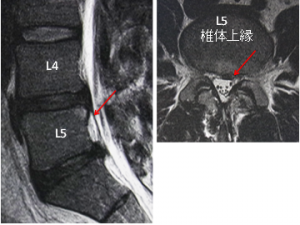

図10-②.L4/5 尾側に移動したヘルニア(赤矢印)